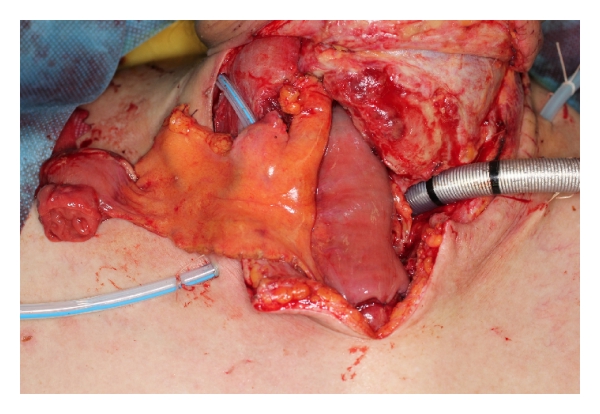

A 62-year-old male underwent surgery for thoracic-cervical esophageal cancer and immediate reconstruction with the retrosternal gastric pull-up technique. The esophagus resection was performed at the level of the 6th cervical vertebra and a bilateral lower segmental neck dissection was performed (nos. 101 to 104) [3]. Therefore, the transverse cervical vessel was exposed in first surgery. Three days after surgery, the patient’s neck exhibited swelling and redness, and the oral side of the pulled-up stomach became necrotic (Figure 1). Thus, 4 days after the primary surgery, the patient underwent debridement of the necrotic tissue and the route of the gastric tube was changed from retrosternal to presternal. The resection of the necrotic gastric tube was 5 cm length, and debridement of necrotic tissue and washing with saline solution were performed. At the same time, immediate free jejunum transfer was performed as salvage surgery (Figure 2). The jejunum was transected at the level of the second jejunal vessel, and the length of harvesting jejunum graft was 15 cm. After trimming of the jejunum graft, the jejunum graft, which was 10 cm length, was placed in the presternal space and joined to the distal end of the cervical esophagus and the proximal end of the residual gastric tube in an end to end anastomosis. The jejunal artery and vein were anastomosed to the right transverse cervical artery and the right internal jugular vein (Figure 3). Because of the short span between first and second surgery, harvesting the free jejunum graft was performed without any difficulty. However, neck dissection during the first surgery caused some adhesion, which resulted in minor technical difficulties during microsurgery. In second time surgery, patient’s vital signs were stable, and no fever or problems in respiratory or circulatory organs were observed. The C-reactive protein level was 22.6 mg/dL, but the white blood cell level was 8.7 × 10³/μL. The patient was able to start oral alimentation 10 days after salvage surgery, and the wound healed completely without complications (Figure 4). Although he died from systemic metastasis from the primary cancer 6 months after the salvage surgery, the patient’s quality of life after surgery, including his food intake, was very good.